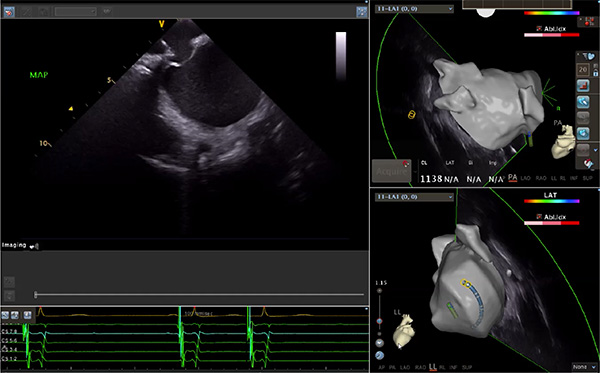

超聲心動圖技術包括常規(guī)經胸超聲(TTE)、經食管超聲(TEE)、心腔內超聲(ICE)、超聲聲學造影(MCE)、三維超聲心動圖等,ICE是一種新興技術——將微型的換能器安裝在心導管的尖端,經由外周血管輸送至心腔內部,換能器發(fā)射聲波,對心臟及其鄰近組織進行實時高質量成像和(或)血流動力學測定的超聲成像技術?;诓煌募夹g原理,心腔內超聲導管被分為兩類:機械旋轉式超聲導管和相控陣超聲導管。目前,臨床上主要應用的是相控陣超聲導管,ICE成像通過術者旋轉導管及操縱導管手柄上的兩個旋鈕來完成。

隨著心腔內超聲的應用更廣,性能也在逐漸優(yōu)化,已從二維成像轉變?yōu)?strong>三維成像,極大增強了引導及可視化能力。二維心腔內超聲支持雙平面或三平面成像,可顯示兩個或三個不同的平面視圖,但醫(yī)生需將這些圖像在腦海中重新構建為三維解剖結構。三維心腔內超聲則可直接呈現(xiàn)三維解剖結構圖,便于醫(yī)生更輕松地開展手術。按照產品發(fā)展方向,預計心腔內超聲還將向更清晰、精準、多功能等方向發(fā)展。